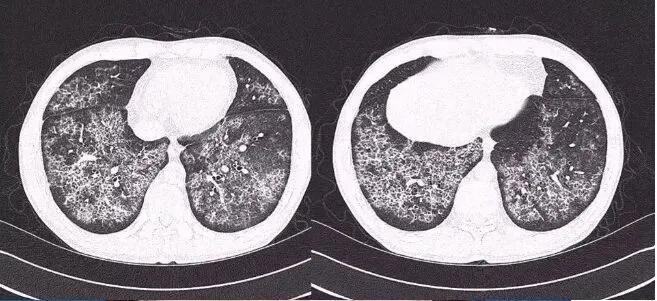

上图是一例小叶中央型肺气肿,不是蜂窝征。

上图是一例肺气肿的病例,CT表现类似于蜂窝肺。